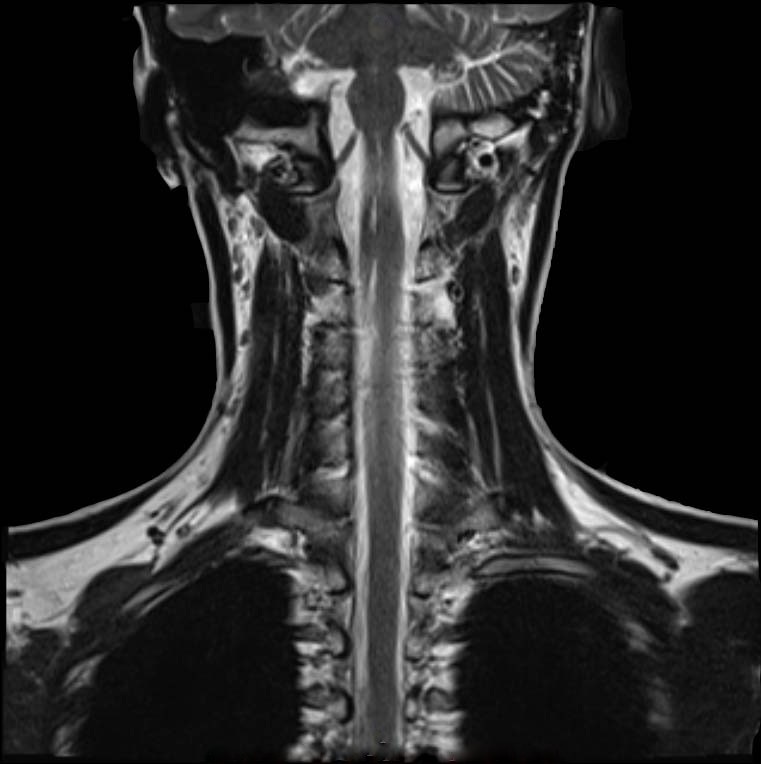

We validated our fast 3D volumetric image reconstruction method on 24 real life T2-MRI data (512×512512512512\times 512 pixels) of human spine with an inter slice gap of 333 to 5mm5𝑚𝑚5mm, and 30 real life T2-MRI data (512×512512512512\times 512 pixels) of human brain collected from Bangur Institute of Neurosciences, S.S.K.M, Kolkata and brain MRI data set of python.

Initially, the 2D2𝐷2D slices are split in 4 sub parts as shown in Figure 2 for a human spine, and the data set in divided in two parts. We use single instruction multiple data architecture using 8 logical cores. In parallel, for each block of sub-image, a 3D3𝐷3D matrix is created which is filled with the corresponding data leaving the specified slice gap in between slices as specified for each set as shown in Figure 3. Then edge preserved kriging interpolation is used to generate the 3d subimages. If we want to visualize these sub-images, then we can apply marching cube with color map and visualize the images as shown in Figure 4 and the complete 3D image for visualisation of full spine is as in Figure 5.

In Figure 7 an example of 3D volumetric reconstruction, visualization as well as slicing are depicted. Figures 9, 11, 12 provide the results of our 3D reconstruction from a sequence of 2D slices for a full spine, a lumbar spine and a brain respectively. We compared the results after slicing with the available ground truth data (Figures 6, 8, 10, 13 for human lumbar along coronal, saggital, axial planes and human brain along sagittal plane respectively) based on mutual information, entropy, root mean square error and structural similarity index (see Appendix D). The average time taken by our 3D3𝐷3D reconstruction fo human spine is 54 seconds, depending on the size of the input data set. The time taken for slicing is a fraction of a second. The average accuracy percentage of our method, as shown in Table 2, is calculated as :